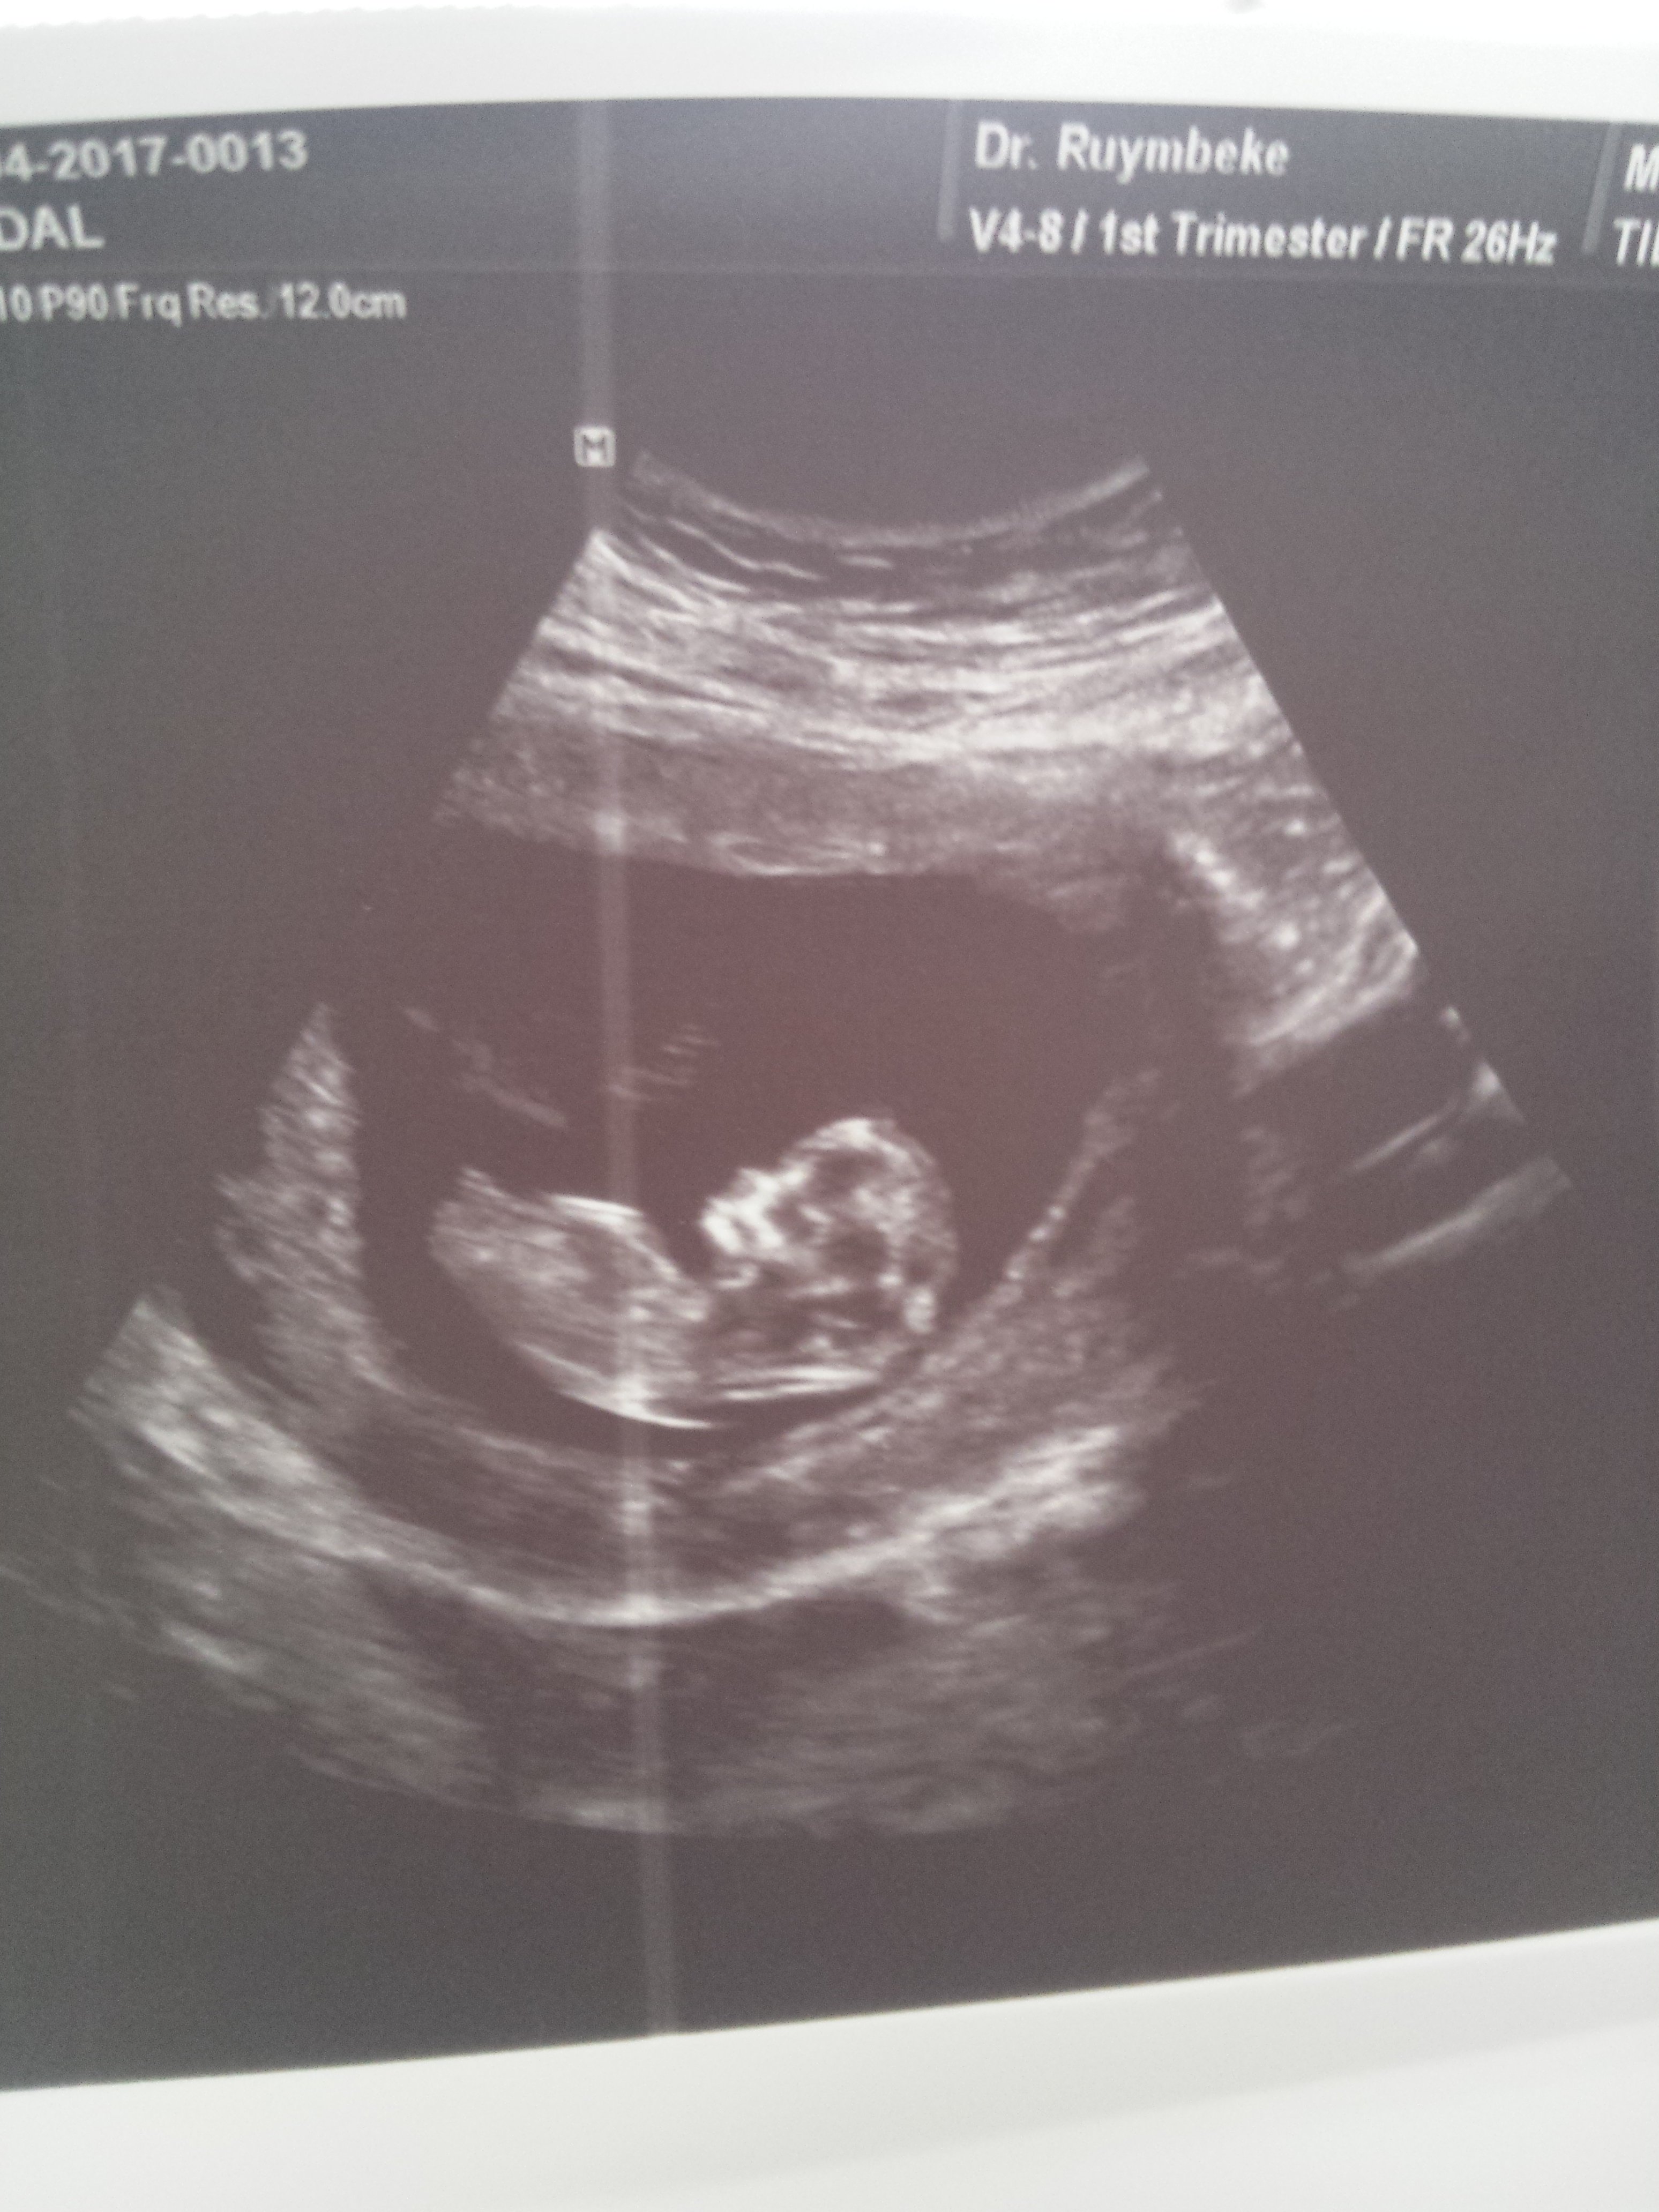

1 1234tmm Yeni Üye Üye 29 Nisan 2017 #266 Ekli dosyayı görüntüle 76265 11+4 dusuncelerinixi alabilirmiyim *BEYZA*' Alıntı: Yorum yaptığınız yerde fotoğraf yükle butonu var.Yüklemeyi ordan yapıcaksınız. Genişletmek için tıkla ... Cok tesekkur canim sanirim oldu.

Ekli dosyayı görüntüle 76265 11+4 dusuncelerinixi alabilirmiyim *BEYZA*' Alıntı: Yorum yaptığınız yerde fotoğraf yükle butonu var.Yüklemeyi ordan yapıcaksınız. Genişletmek için tıkla ... Cok tesekkur canim sanirim oldu.

Uzman SühaN Administrator 29 Nisan 2017 #267 Merhaba, Nub çıkıntısı pek net değil fakat bebeğinizin cinsiyetinin kız olduğunu düşünüyorum.Sağlıklı gebelik geçirmeniz dileği ile.

Merhaba, Nub çıkıntısı pek net değil fakat bebeğinizin cinsiyetinin kız olduğunu düşünüyorum.Sağlıklı gebelik geçirmeniz dileği ile.